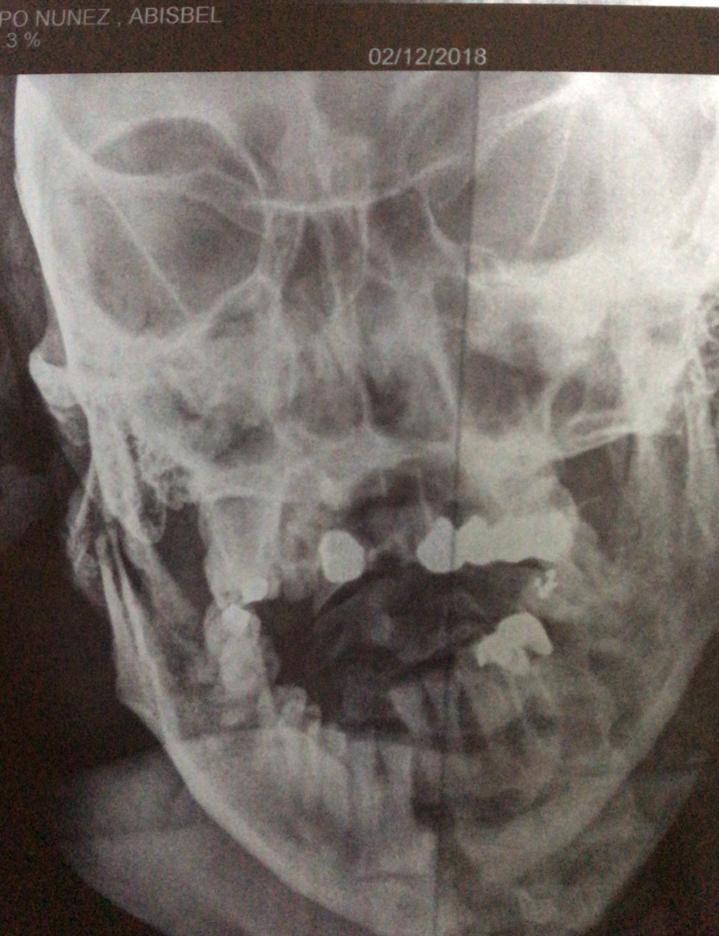

Se supo que los agentes policiacos realizaron una llamada al area jurídica de la Policía Estatal Preventiva donde un asesor, les dijo que trasladaran a dicho sujeto a las instalaciones de la Policia Municipal y lo consignaran por una falta administrativa, en tanto esperaban la llegada de una ambulancia para que le brindaran la atención medica pre hospitalaria debido a las lesiones que presentaba; fue así que los paramédicos de al Unidad de Respuesta a Emergencias Medicas (UREM) arribaron al sitio pasadas las 7:15 y brindaron el traslado de la mujer a la clínica del Seguro Social donde se le atendió pero debido a la gravedad de sus lesiones fue canalizada a la clínica privada Independencia, en la que se determino que sufrir explosion de sus párpados, fractura multiple de tabique nasal, fractura de quijada, fractura de craneo, diversas fracturas en costillas, incluso presento señas de haber sido torturada ya que le arrancaron las uñas de las manos.

Addisbel P.N. se mantiene hospitalizada y en un coma inducido en una clínica de la zona norte de la entidad, siendo custodiada por autoridades para evitar sufra algún otro ataque, en tanto los agentes de la policia estatal y el asesor jurídico de la SSP, están siendo investigados y en caso de ser participes de un hecho de corrupción se pondrá todo el peso de la ley en su contra.